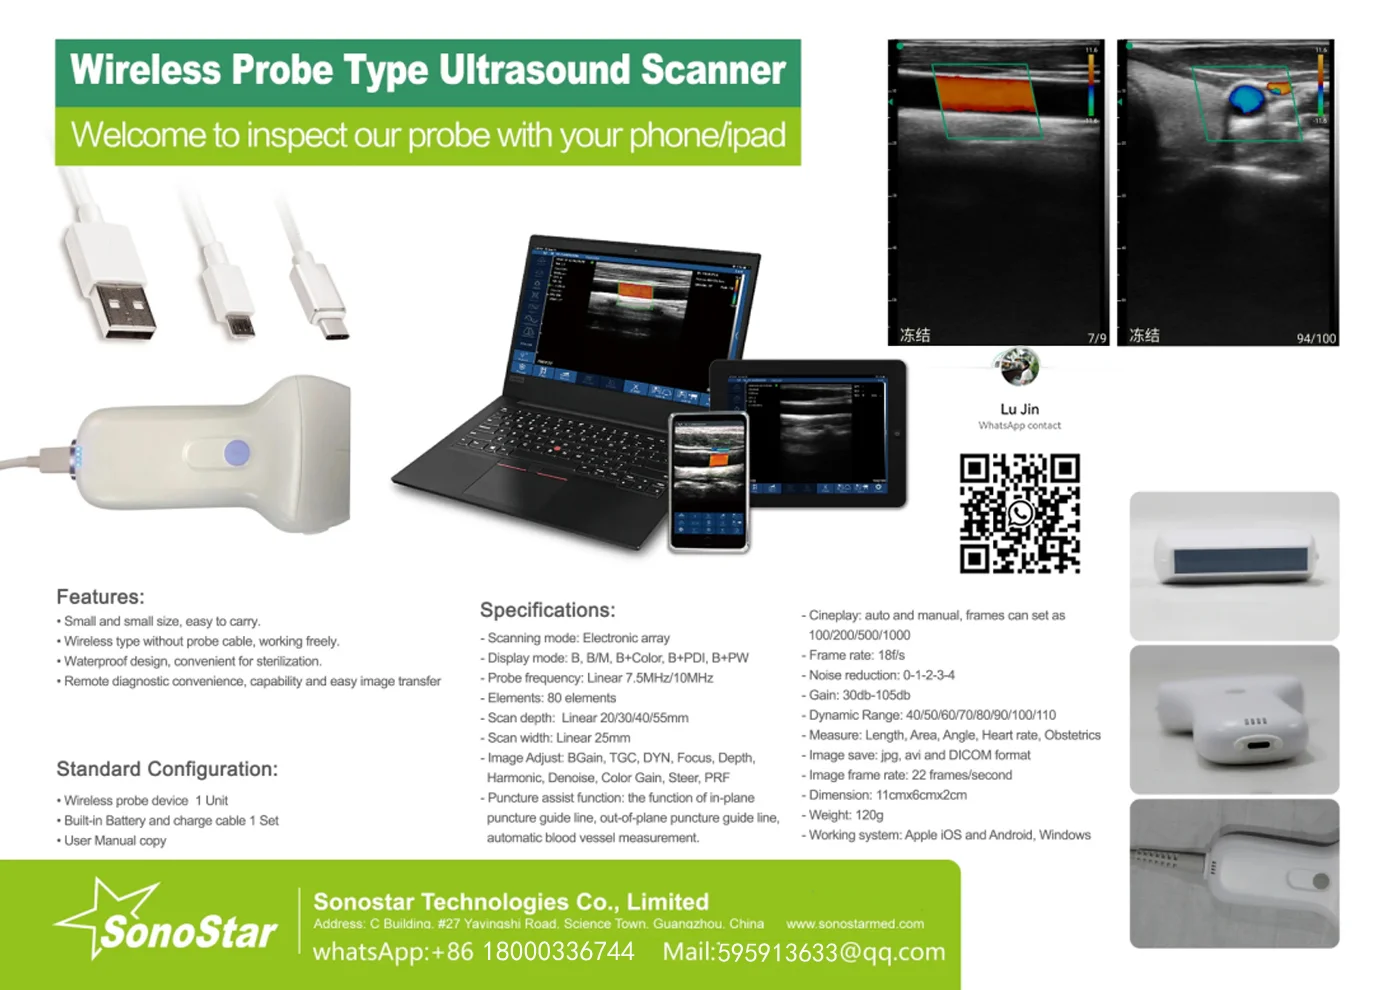

Linear Probe Parameters

-Scanning mode: Electronic array

-Display mode: B, B/M

-Probe element: 80

-Channel of RF circuit board: 16

-Frequency: 7.5MHz/10MH

-Scan depth: 20/40/60/100mm

-Head width: 40mm

-Image Adjust: BGain, TGC, DYN, Focus, Depth, Harmonic, Denoise, Color Gain, Steer, PRF

-Cineplay: auto and manual, frames can set as 100/200/500/1000

-Puncture assist function: the function of in-plane puncture guide line, out-of-plane puncture guide line, automatic blood vessel measurement.

-Measure: Length, Area, Angle, heart rate, Obstetrics

-Image save: jpg, avi and DICOM format

-Image frame rate: 18 frames / second

-Battery working time: 3~5 hours(according to different probe and whether keep scan)

-Battery charge: by USB charge or wireless charge, take 2 hours

-Dimension: 156×60×20mm

-Weight: 220g~250g

-Wifi type: 802.11g/20MHz/5G/450Mbps

-Working system: Apple iOS and Android, Windows 10 system

Standard Configuration:

-Main Host(probe) 1 Unit

-Internal Battery and charger 1 Set

-Non-slip lanyard

Convex Probe Pictures:

Linear Probe Pictures:

This machine can be used for both humans and animals: